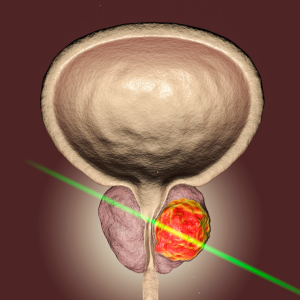

Dr. Goel is adept at treating a wide range of urological conditions, including kidney stones, urinary tract infections, prostate disorders, and male infertility. He is skilled in performing minimally invasive surgeries, which offer quicker recovery times and reduced discomfort for patients. His expertise extends to oncological urology, where he provides comprehensive care for cancers of the kidney, bladder, prostate, and testicles, working closely with oncologists to ensure optimal outcomes for his patients.

Prostate Care

Uro-Oncology